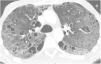

Reticulonodular infiltrates are seen on chest radiographs, and as they progress, ground-glass opacities and consolidations may appear. The main findings on CT are ground-glass opacities, centrilobular nodules and air cysts, which are present in up to 80% of cases (Fig. 10). Subpleural nodules, septal and peribronchovascular thickening, and lymphadenopathy may also be seen. Air cysts are few in number, usually less than 3cm, are frequently seen in ground-glass areas, and are random in distribution, although they are often seen adjacent to a vessel or bronchus and can also be subpleural.44,45 On follow-up CT, nodules and ground-glass opacities may disappear, but cysts may persist.46 Partial airway obstruction secondary to peribronchiolar lymphocytic infiltration with distal air trapping has been hypothesised as a pathogenic mechanism of these cysts. There may also be ischaemia due to vascular obstruction.9,11,40,43–45 Identification of these cysts is useful for the differential diagnosis with cellular NSIP and lymphoma, but can be difficult both with CT and pathology.40,42,43,47 In patients with LIP associated with Sjögren’s disease, the appearance of large nodules should lead to suspicion of amyloidosis—especially if the nodules are calcified—or lymphoma.10,40 (Fig. 11) On CT, hypersensitivity pneumonitis can present very similar findings to those of LIP, with cysts in up to 13% of cases.8 Differentiation can also be difficult for the pathologist, but usually the clinical context helps with the differential diagnosis.

Lymphoid interstitial pneumonia (LIP) in a 65-year-old woman with Sjögren's syndrome. (A) The HRCT image at the level of the pulmonary hila demonstrates multiple thin-walled air-filled cystic images. Also note the presence of ground glass opacities (arrow). (B) The image reconstruction in the coronal plane reveals the diffuse distribution of the findings.